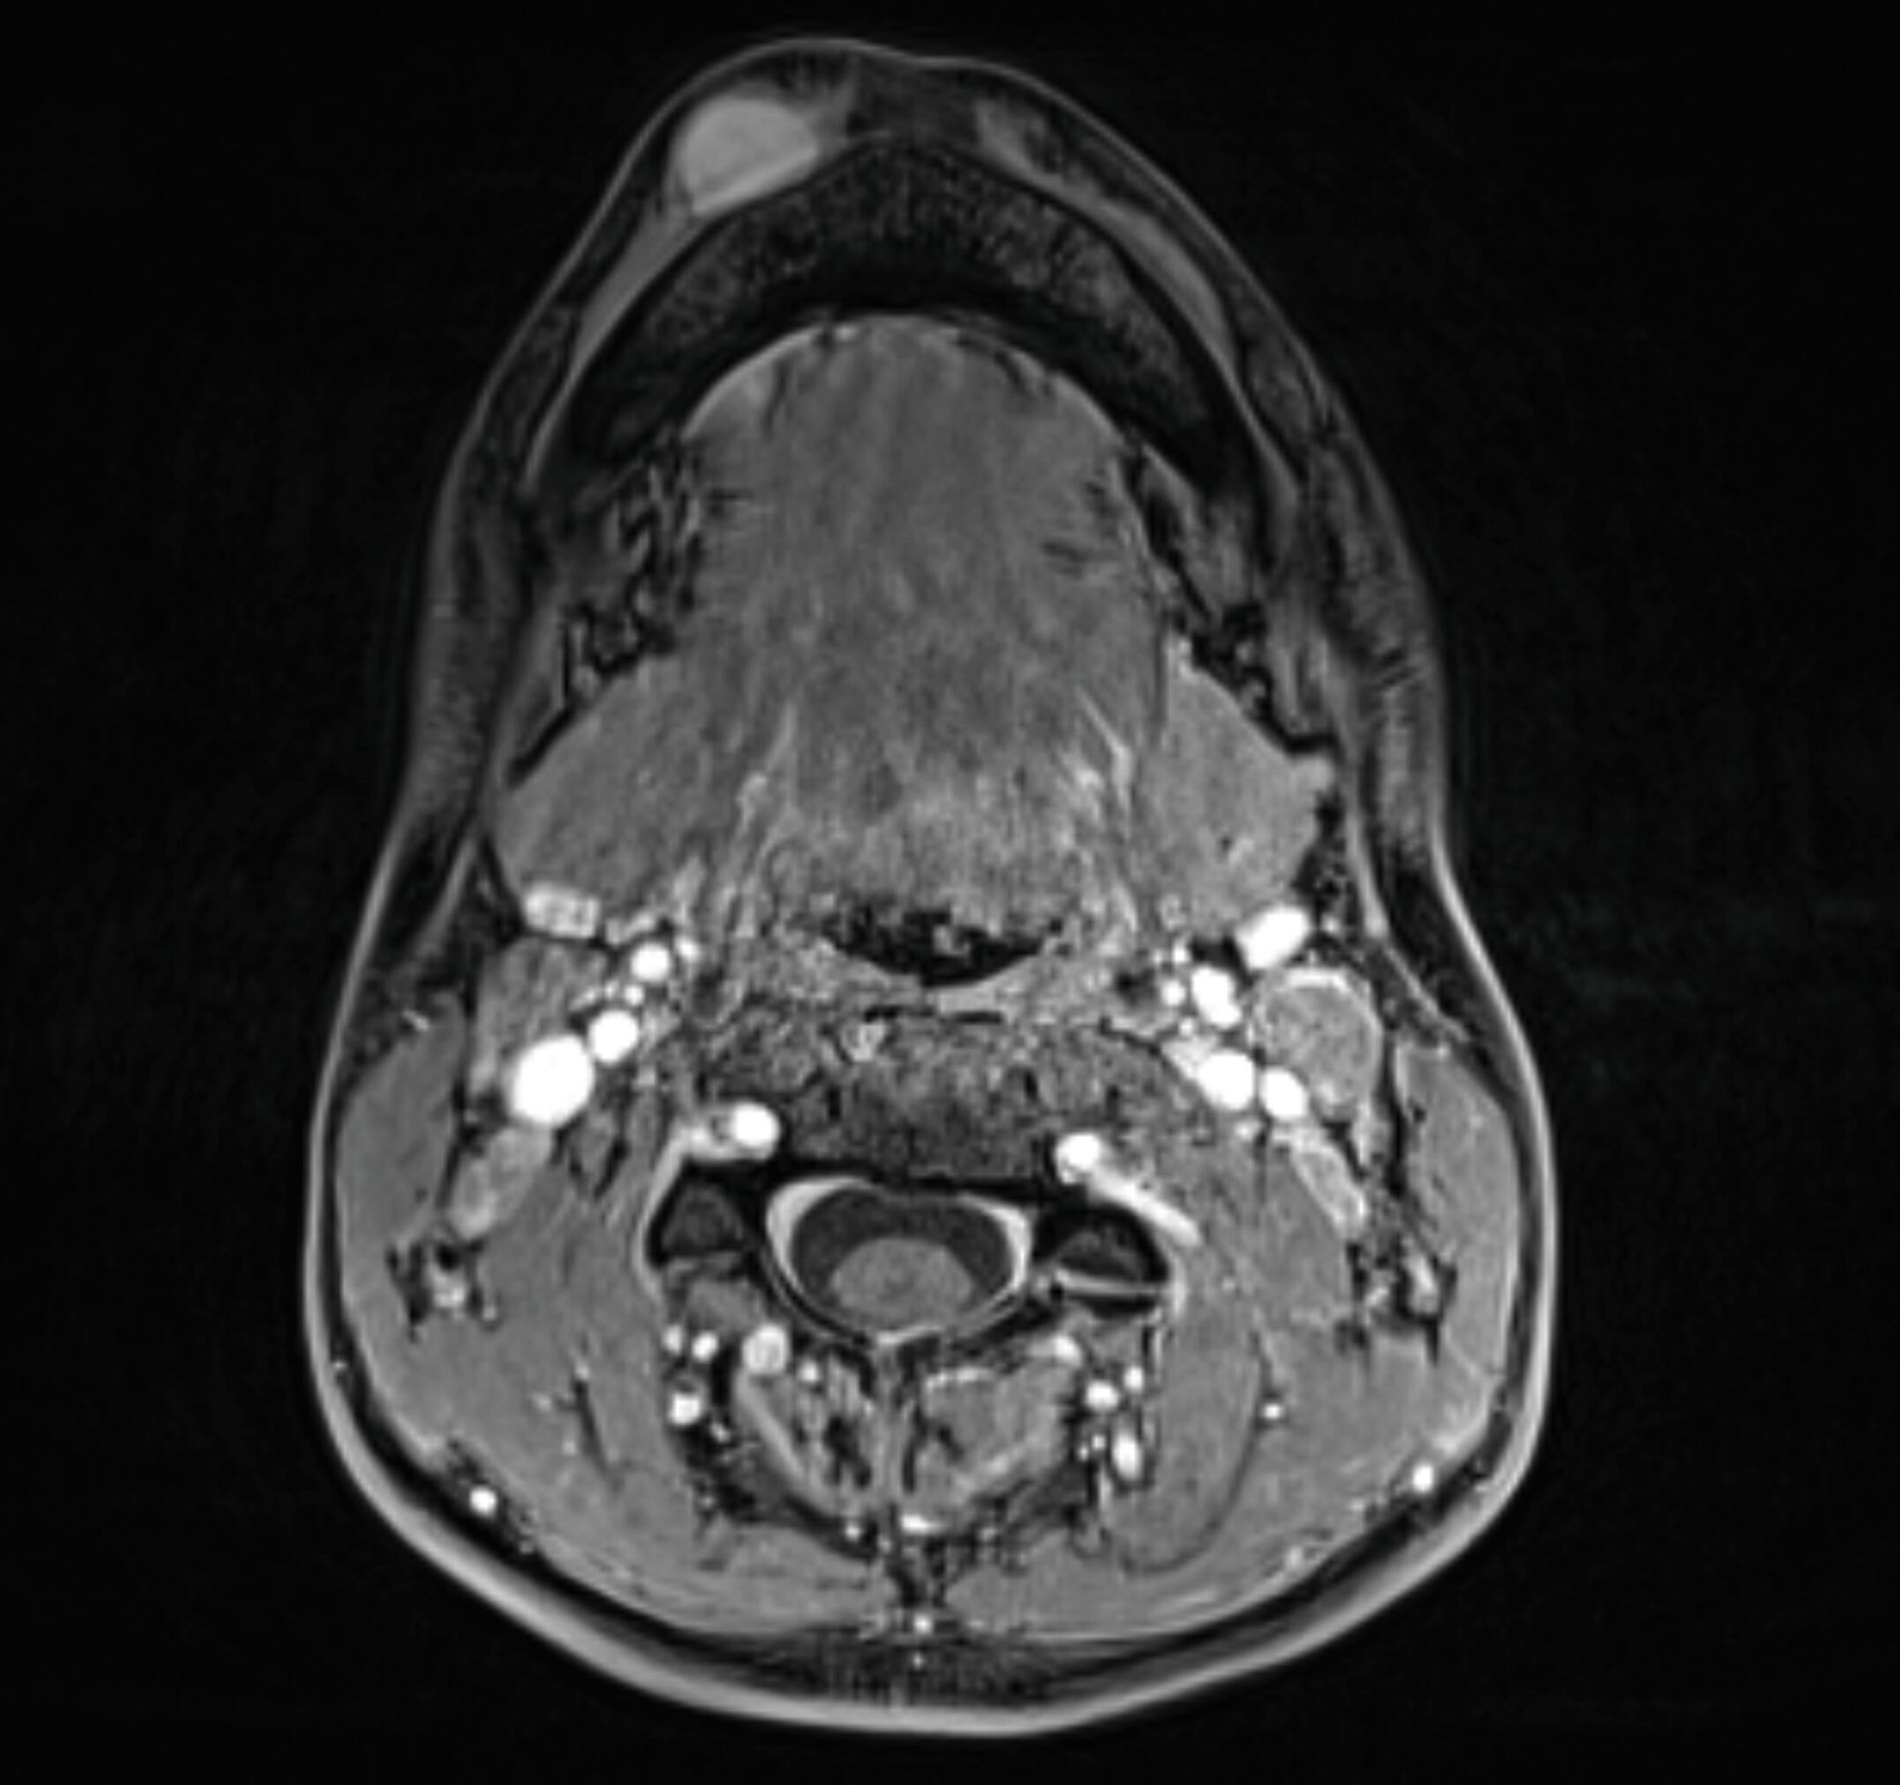

Eine Unterbrechung der Kortikalis oder Abszessformationen ergaben sich nicht. Zur erweiterten Diagnostik erfolgte die Anfertigung einer Magnetresonanztomografie des Kopf-Hals-Bereichs. Hier zeigte sich bildmorphologisch ein zur Muskulatur isointenser Tumor mit deutlicher Kontrastmittelaufnahme, den Unterkiefer basal teilweise umschlingend, jedoch nicht destruierend (Abbildungen 3 und 4).